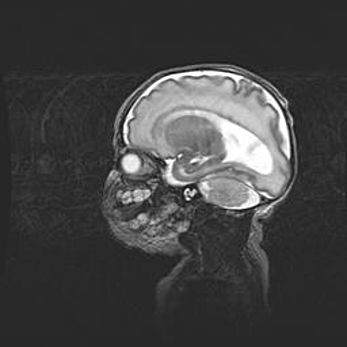

Аномалия Денди-Уокера. Признаки гипоплазии мозолистого тела.

Возраст: 5 месяцев 3 дня

Вес: 5550 г

Пол: мужской

Окружность головы: 39 см

Срок гестации: 40 недель

Аномалия Денди-Уокера – это порок развития головного мозга, для которого характерна триада симптомов: гипотрофия или аплазия червя мозжечка и/или полушарий мозжечка, расширение четвёртого желудочка с формированием ликворной кисты задней черепной ямки, гипертензионная гидроцефалия различной степени.

Гипоплазия мозолистого тела относится к дефектам внутриутробного этапа развития мозговой ткани, возникающим в процессе закладки структур головного мозга, что происходит на начальных этапах развития эмбриона.